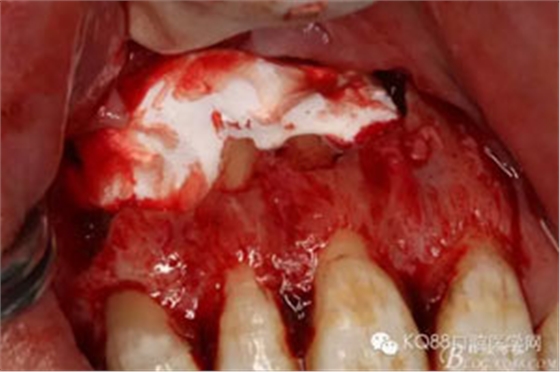

圖11.骨腔填塞膠原蛋白

圖12.縫合創(chuàng)口